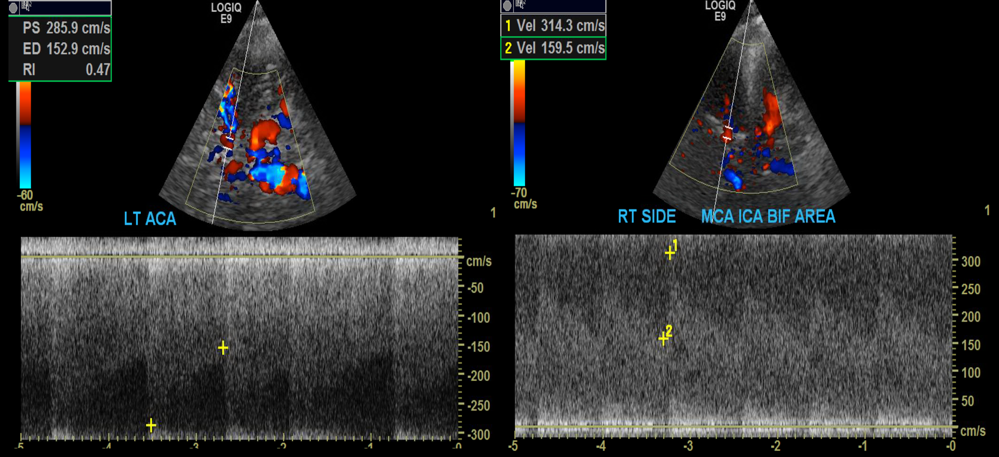

16 yo F with SCD showing elevated PSV in the LT ACA and RT MCA. On MR Angio she was found to have stenoses at both these sites.